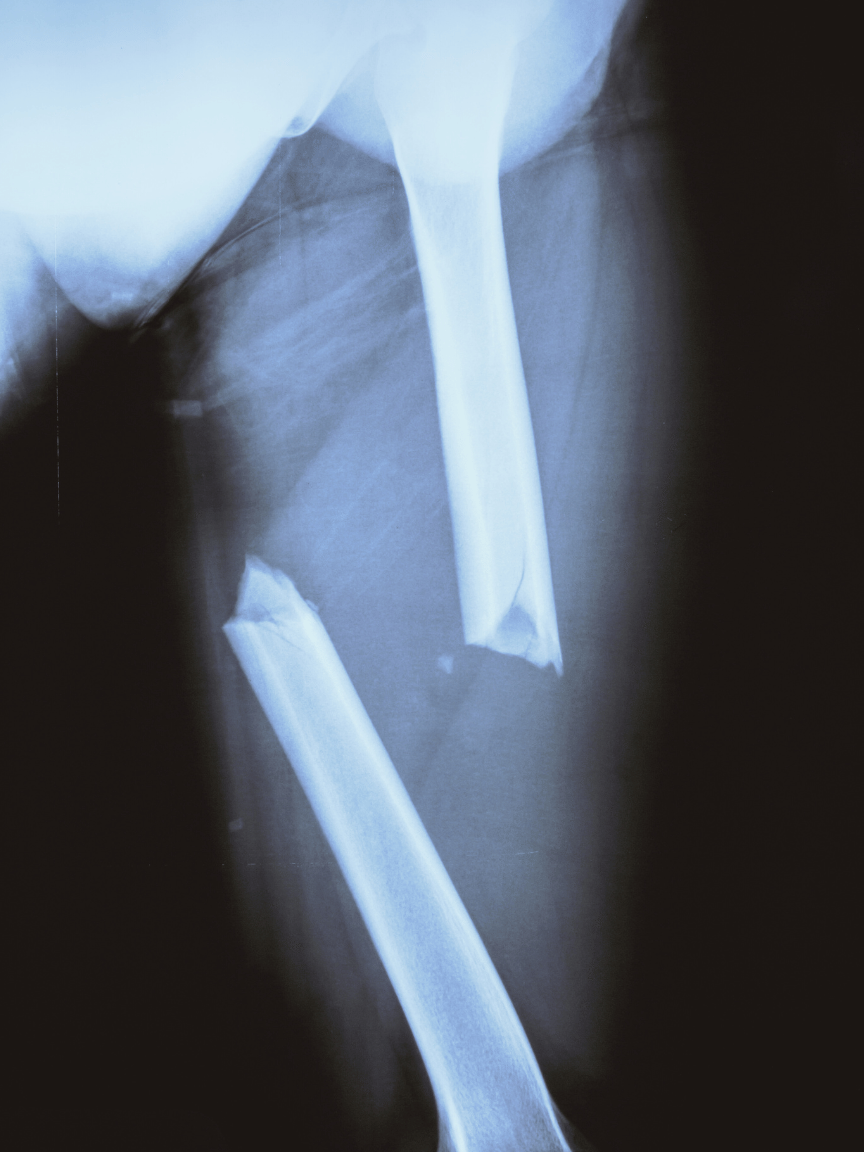

The first image is a very displaced apparent femur fracture that will require surgery to better align the bone and keep it in place for proper healing. The second image is that of a nondisplaced distal radius fracture.

Image of an x-ray of a displaced child femur fracture

A displaced femur fracture.